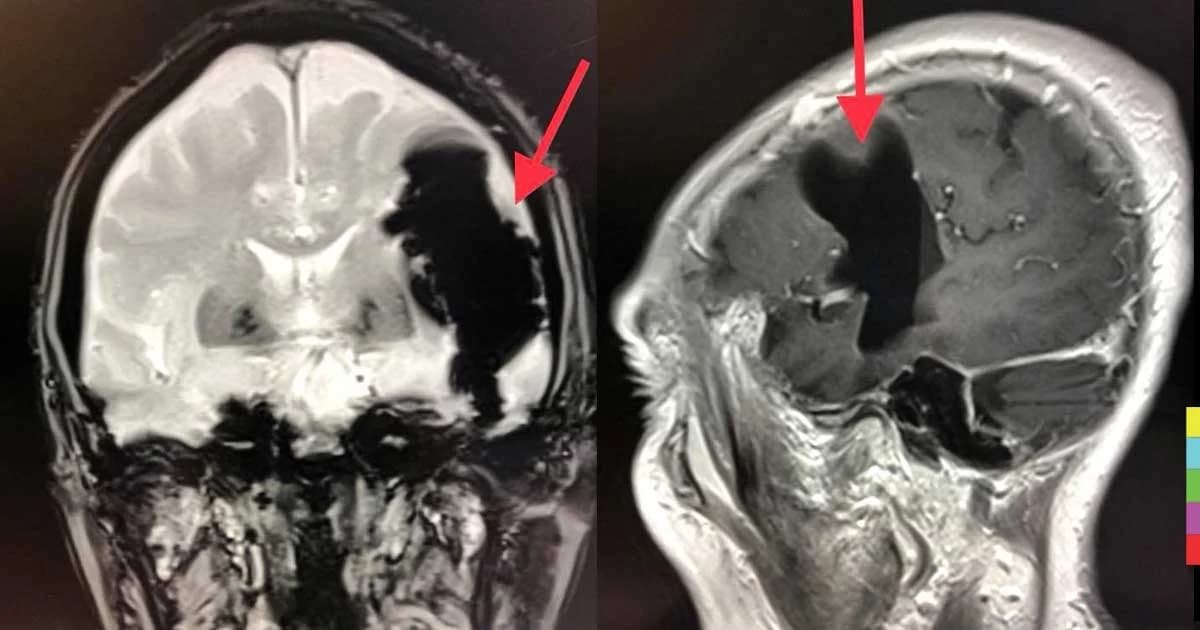

“ผู้ป่วยหญิงไทยอายุ 82 ปี เป็นโรคเบาหวานและไขมันสูง มาหาผมเมื่อ ธ.ค. 2559 ด้วยอาการพูดไม่ชัด นึกคำพูดไม่ออก 3 วัน ได้ทำ MRI (คลื่นแม่เหล็ก) สมอง พบมีลม (air pocket) ในเนื้อสมองข้างซ้ายขนาด 7x4x3.2 ซม. (ดูลูกศรในรูปภาพ) ติดตามไปอาการดีขึ้นช้าๆ ปัจจุบันปกติดี

ผู้ป่วยตอบว่า ก่อนไม่สบาย กำลังจะสั่งน้ำมูก เกิดจามขณะเอามือบีบจมูก เอานิ้วอุดรูหูข้างขวาและเม้มปากพร้อมๆ กัน หลังทำหูข้างซ้ายอื้อและมีเสียงดัง ลมจากการจามออกทางจมูกปากไม่ได้ คงผ่านจากท่อในปากเข้าหูชั้นกลางด้านซ้ายแล้วทะลุผ่านกระโหลกใต้สมองเข้าสมองด้านซ้าย (ดูลูกศรในรูปภาพ)